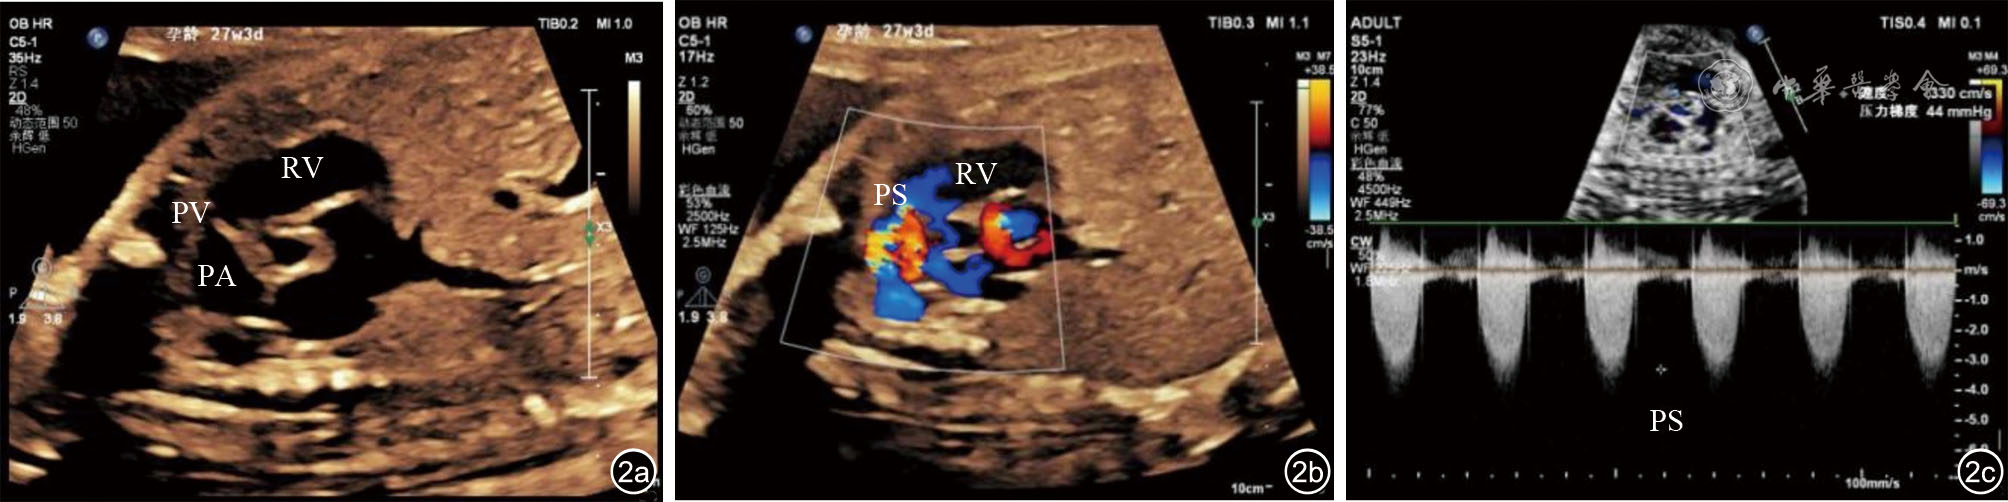

王锟, 张晓花, 伊凤蕊, 等. 室间隔完整型危重肺动脉瓣狭窄的产前超声心动图特征分析 [J]. 中国临床医学影像杂志, 2022, 33(7): 493-497.